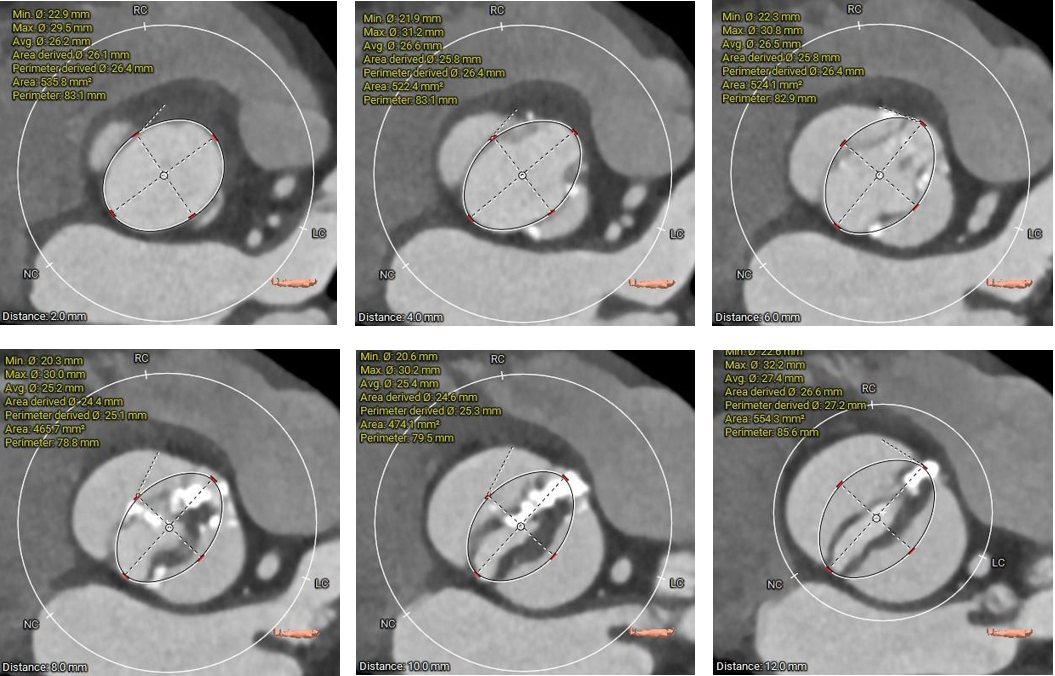

1.主动脉瓣瓣环周长83.8mm,平均周长径26.7mm。

3. 左右冠开口高度可,左冠瓣叶长度<瓣叶附着缘到冠脉开口处,右冠瓣叶长度>瓣叶附着缘到冠脉开口处,瓦氏窦、窦管交界内径尚可,升主动脉瘤样性扩张(最大直径52.2mm) 。

4. 流出道呈敞口型,心室腔偏大 。

1. Type0型二叶式主动脉瓣,瓣叶中度钙化伴增厚,钙化分布不均匀,LVOT呈敞口形,结合瓦氏窦、STJ,升主综合预估瓣膜锚定力难度适中,存在人工瓣膜形变、移位、瓣周漏风险。

3.推荐选择23mm球囊预扩张,推荐预装AV29瓣膜。

4.瓣膜释放高度推荐瓣环上0--2mm左右。释放后建议调整至正交位 RAO35°CAU31°进一步确定人工瓣膜形态。